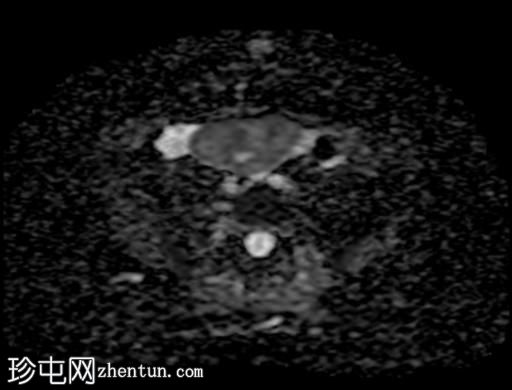

DWI

8.jpg

ADC

9.jpg